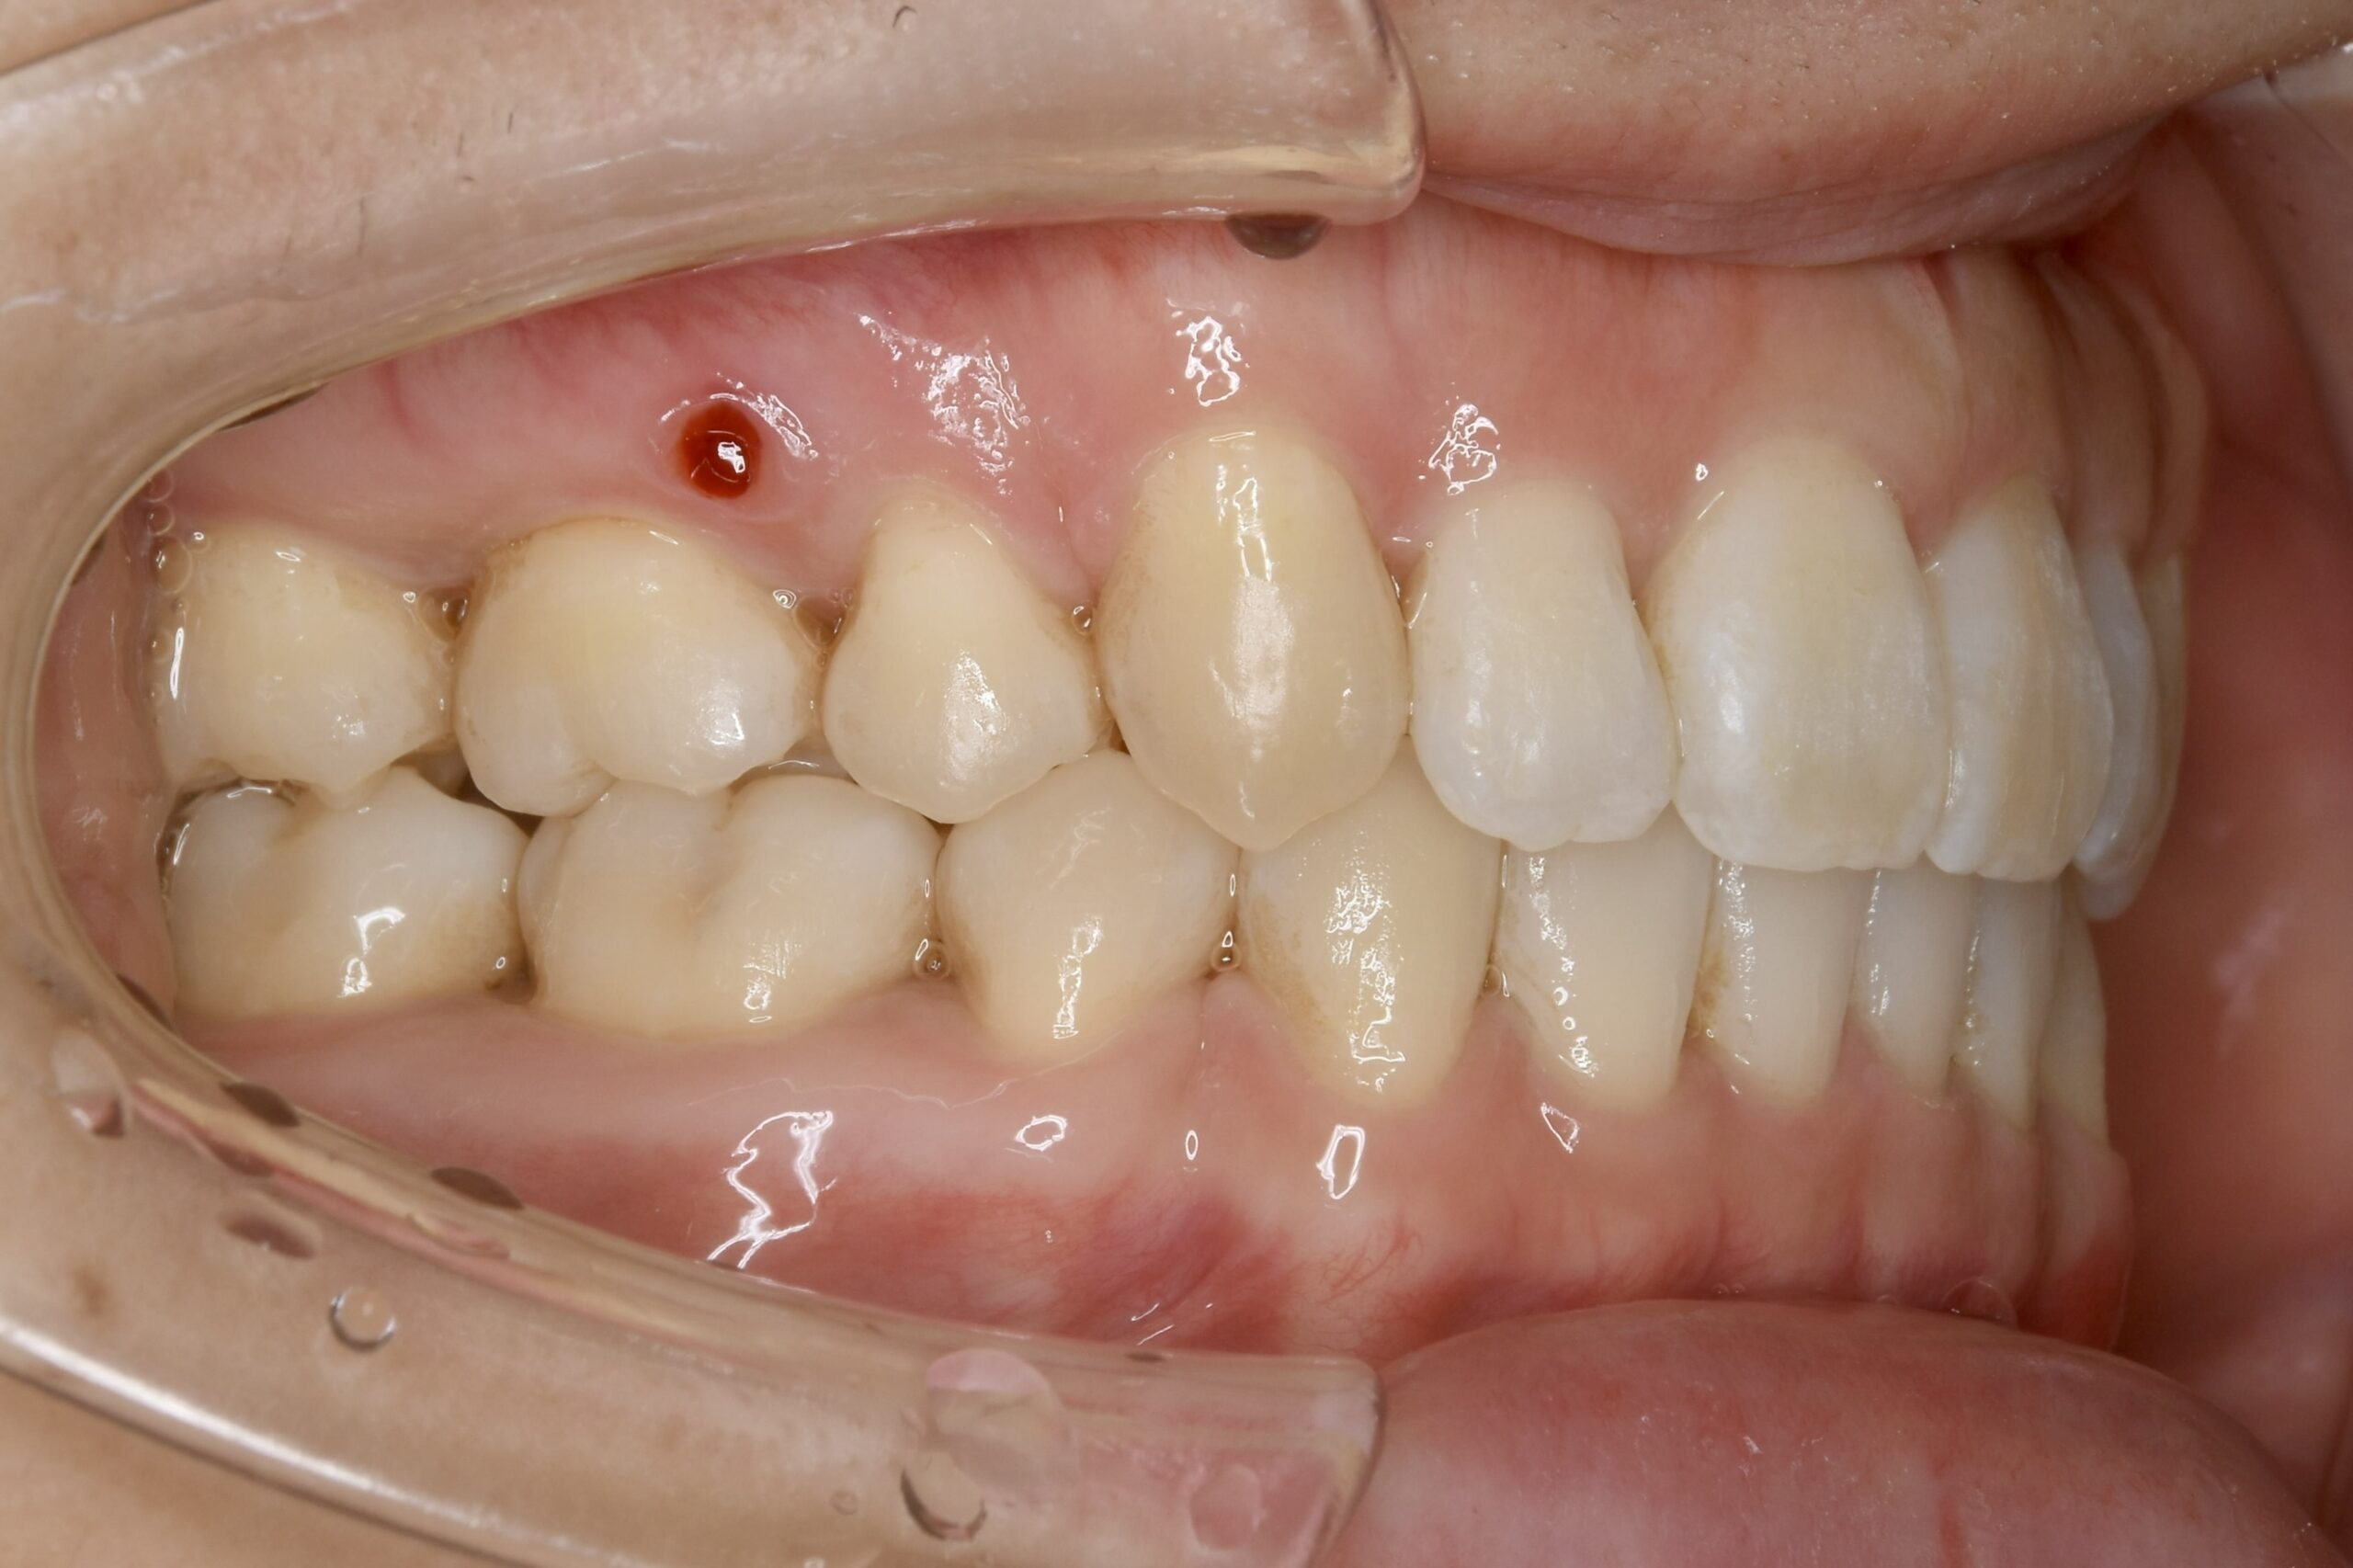

| 主訴 | 写真を見て歯並びが気になる。特に下の前歯はガタガタが強く治したい。 |

|---|---|

| 診断名・主な症状 | 叢生 |

| 年齢 | 19歳 |

| 治療内容 | 上下とも歯並びの幅を広げることでできたスペースを利用して、ガタガタを解消しました。 |

| 使用装置 | 表側矯正(ワイヤー) 矯正用ミニインプラント |

| 抜歯部位 | 抜歯なし |

| 治療期間 | 1年10ヶ月 |

| 通院回数 | 25回 |

| 費用 | 91万円程度(税別) 220 |

| リスク・副作用 | 痛み、歯肉退縮、歯根吸収、抜歯に伴う出血や腫れが生じることがあります。 |